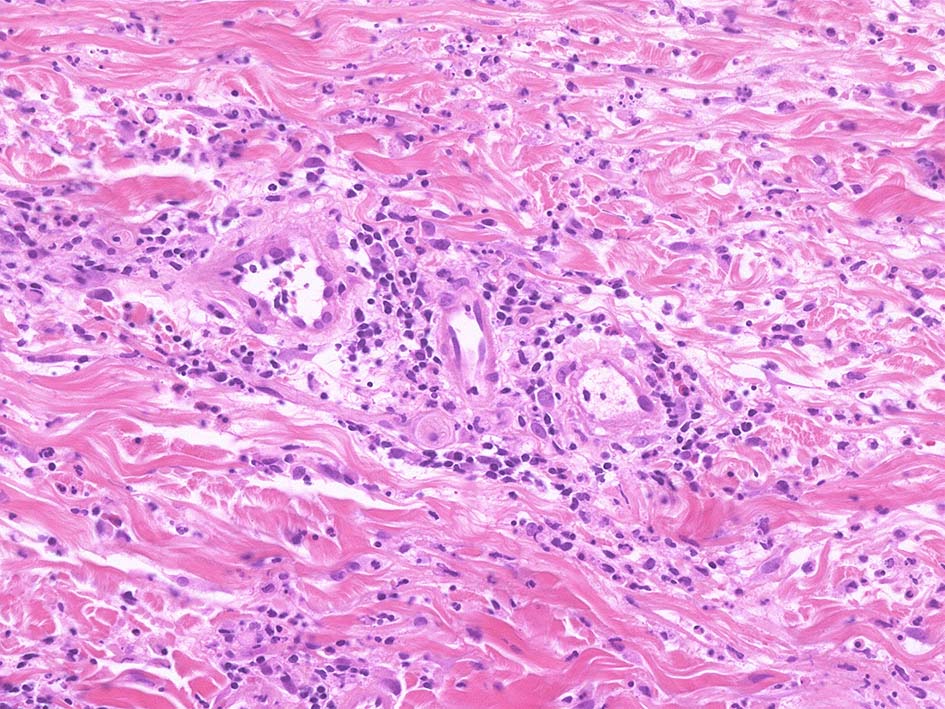

Case02 前胸部皮膚

73 year old male

lt

骨髄異形成症候群で入院中. 発熱, 関節痛に加えて四肢, 胸部など上半身に潰瘍形成をともなう浮腫性紅斑が出現してきた. 皮下硬結あり. Sweet症候群と診断.

中央に黒色痂皮を示す紅斑. 硬結の強い部位から生検される.

HE x40. 表皮下水疱あり. 真皮上層は浮腫状. 真皮から皮下組織にかけて, 多数の好中球が浸潤している. リンパ球, 好酸球が混在, 核破砕物を貪食するマクロファージが増加. 膠原線維にはところどころ変性が見られる.

真皮上層には核破砕物が多く, 好中球浸潤が認められる. 慢性炎症性細胞も浸潤している.

フィブリノイド壊死を呈する血管炎は認められない.

皮下脂肪織炎病変には局所的なhemophagocytosisが認められる. 血管にはfibrinoid necrosisは見られない。